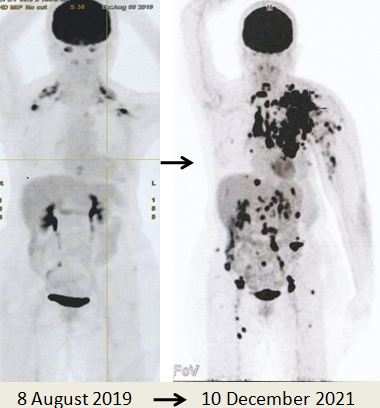

Karena metastasis seperti yang ditunjukkan pada pemindaian PET yang dilakukan pada 10 Desember 2021, Lucy tidak punya pilihan selain melanjutkan kemoterapi. Memang kanker telah menyebar luas.

Bandingkan ketiga gambar ini :

Kiri: Setelah operasi Lucy menjalani terapi alternatif, menolak kemoterapi. Hasilnya adalah metastasis luas (tengah).

Kanan: Lucy tidak punya pilihan selain menjalani kemoterapi. Hasil dari 6 siklus kemoterapi sungguh luar biasa! Selama lebih dari 25 tahun saya berurusan dengan pasien kanker, saya belum pernah melihat hasil kemoterapi yang luar biasa seperti ini. Salut dengan ahli onkologi! Anda menyelamatkan Lucy!

Seperti yang ditunjukkan oleh hasil kasus ini, Lucy telah mengambil jalan yang salah. Dua puluh bulan setelah melakukan apa yang menurutnya benar, kanker Lucy menyebar seperti api liar. Ada metastasis ke kelenjar getah bening regional, nodul subkutan, paru-paru, peritoneum dan tulang (lihat gambar di atas).

Saya mungkin mengatakan saya tidak percaya pada apa yang saya lihat di PET scan – itu benar-benar bencana yang mengerikan. Lucy telah melakukan kesalahan yang tragis.